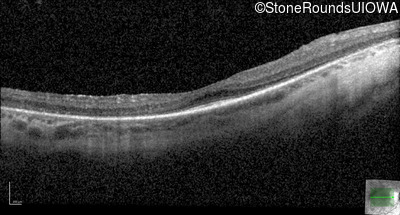

Optical Coherence Tomography - Right - 20/50 -2

Exemplar / OCT Stack

OCT Stack